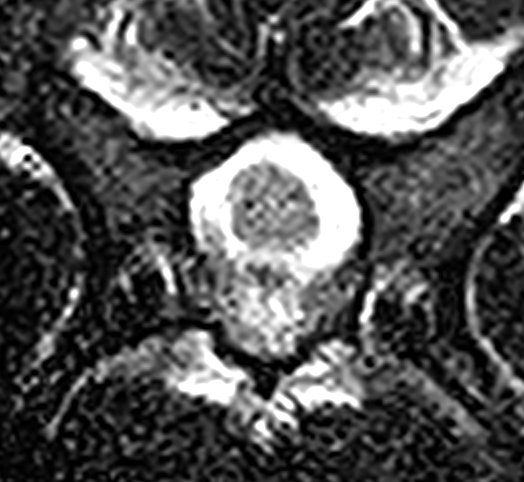

MRI画像検査です。頚椎2−3の圧迫が確認されました。

頚椎3−4での圧迫が確認されました。

椎体中央部の正常な脊髄です。脊髄周囲には脳脊髄液があり、狭窄がないのがわかります。

X線CT画像検査です。特に頚椎2−3領域で左右からの重度の圧迫が確認されました。椎間板の問題ではなく、骨自体の形・形態異常からくるものと判断しました。